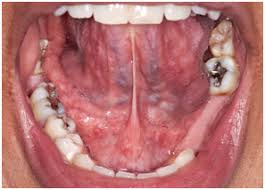

Tongue Tied Ankyloglossia Tongue Tied Or Ankyloglossia Is When A Person Has A Short Lingual Frenum Membrane Connecting Tongue Tie Tongue Breastfeeding Help

Double Tongue Appearance Due To Swelling Of The Floor Of Mouth Medizzy Journal